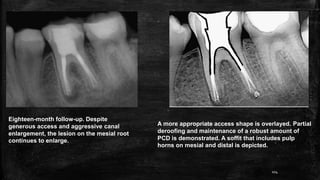

Eighteen-month follow-up. Despite

generous access and aggressive canal

enlargement, the lesion on the mesial root

continues to enlarge.

A more appropriate access shape is overlayed. Partial

deroofing and maintenance of a robust amount of

PCD is demonstrated. A soffit that includes pulp

horns on mesial and distal is depicted.

104